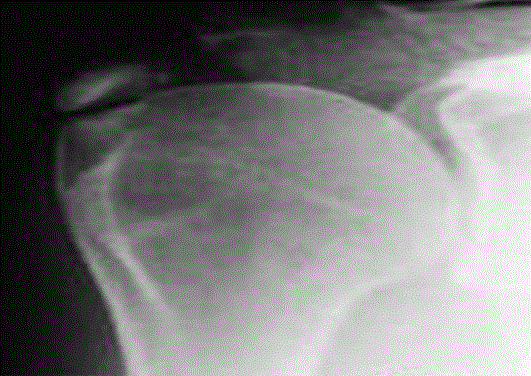

Η διάγνωση της ασβεστοποιού τενοντίτιδας είναι πολύ εύκολη καθώς είναι μια από τις παθολογίες του ώμου η οποία φαίνεται ξεκάθαρα σε απλή ακτινογραφία αλλά και στον υπέρηχο (σε έμπυρα χέρια). Συγκεκριμένα, δίπλα στην κεφαλή του βραχιονίου στην περιοχή των μαλακών μορίων, φαίνεται συνήθως ξεκάθαρα μια λευκή περιοχή σαν ένα κομμάτι βαμβάκι. Το σύνηθες ανατομικό σημείο της παθολογίας αυτής είναι πάλι στον τένοντα του υπερακανθίου.